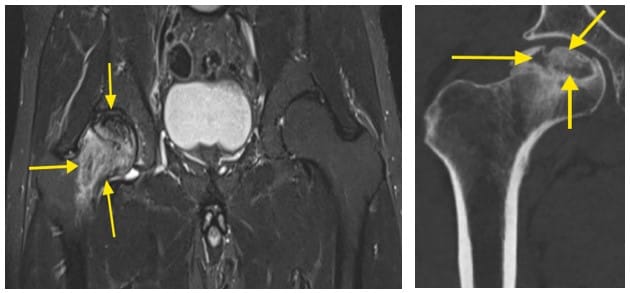

Diagnosticul paraclinic – examinarea radiologică a șoldului ne poate arăta în faze mai avansate modificări de structură ale capului femural, colapsul acestuia și, în stadiul final, degenerarea întregii articulații. Examinarea RMN este investigația paraclinică de elecție în cazul acestei patologii, putând face diferența între osul sănătos, edemul osos și osul deja necrozat. Examinarea CT evidențiază cu acuratețe mai mare dacă suprafața osoasă a capului femural s-a prăbușit, fiind necesară pentru diferențierea anumitor stadii de evoluție.

Imagini RMN care evidențiază necroza capului femural; imaginea din partea dreaptă – efectuare foraje cap femural.

Examinare RMN – necroză cap femural drept, cap femural stâng sănătos.

Examinare CT a necrozei.